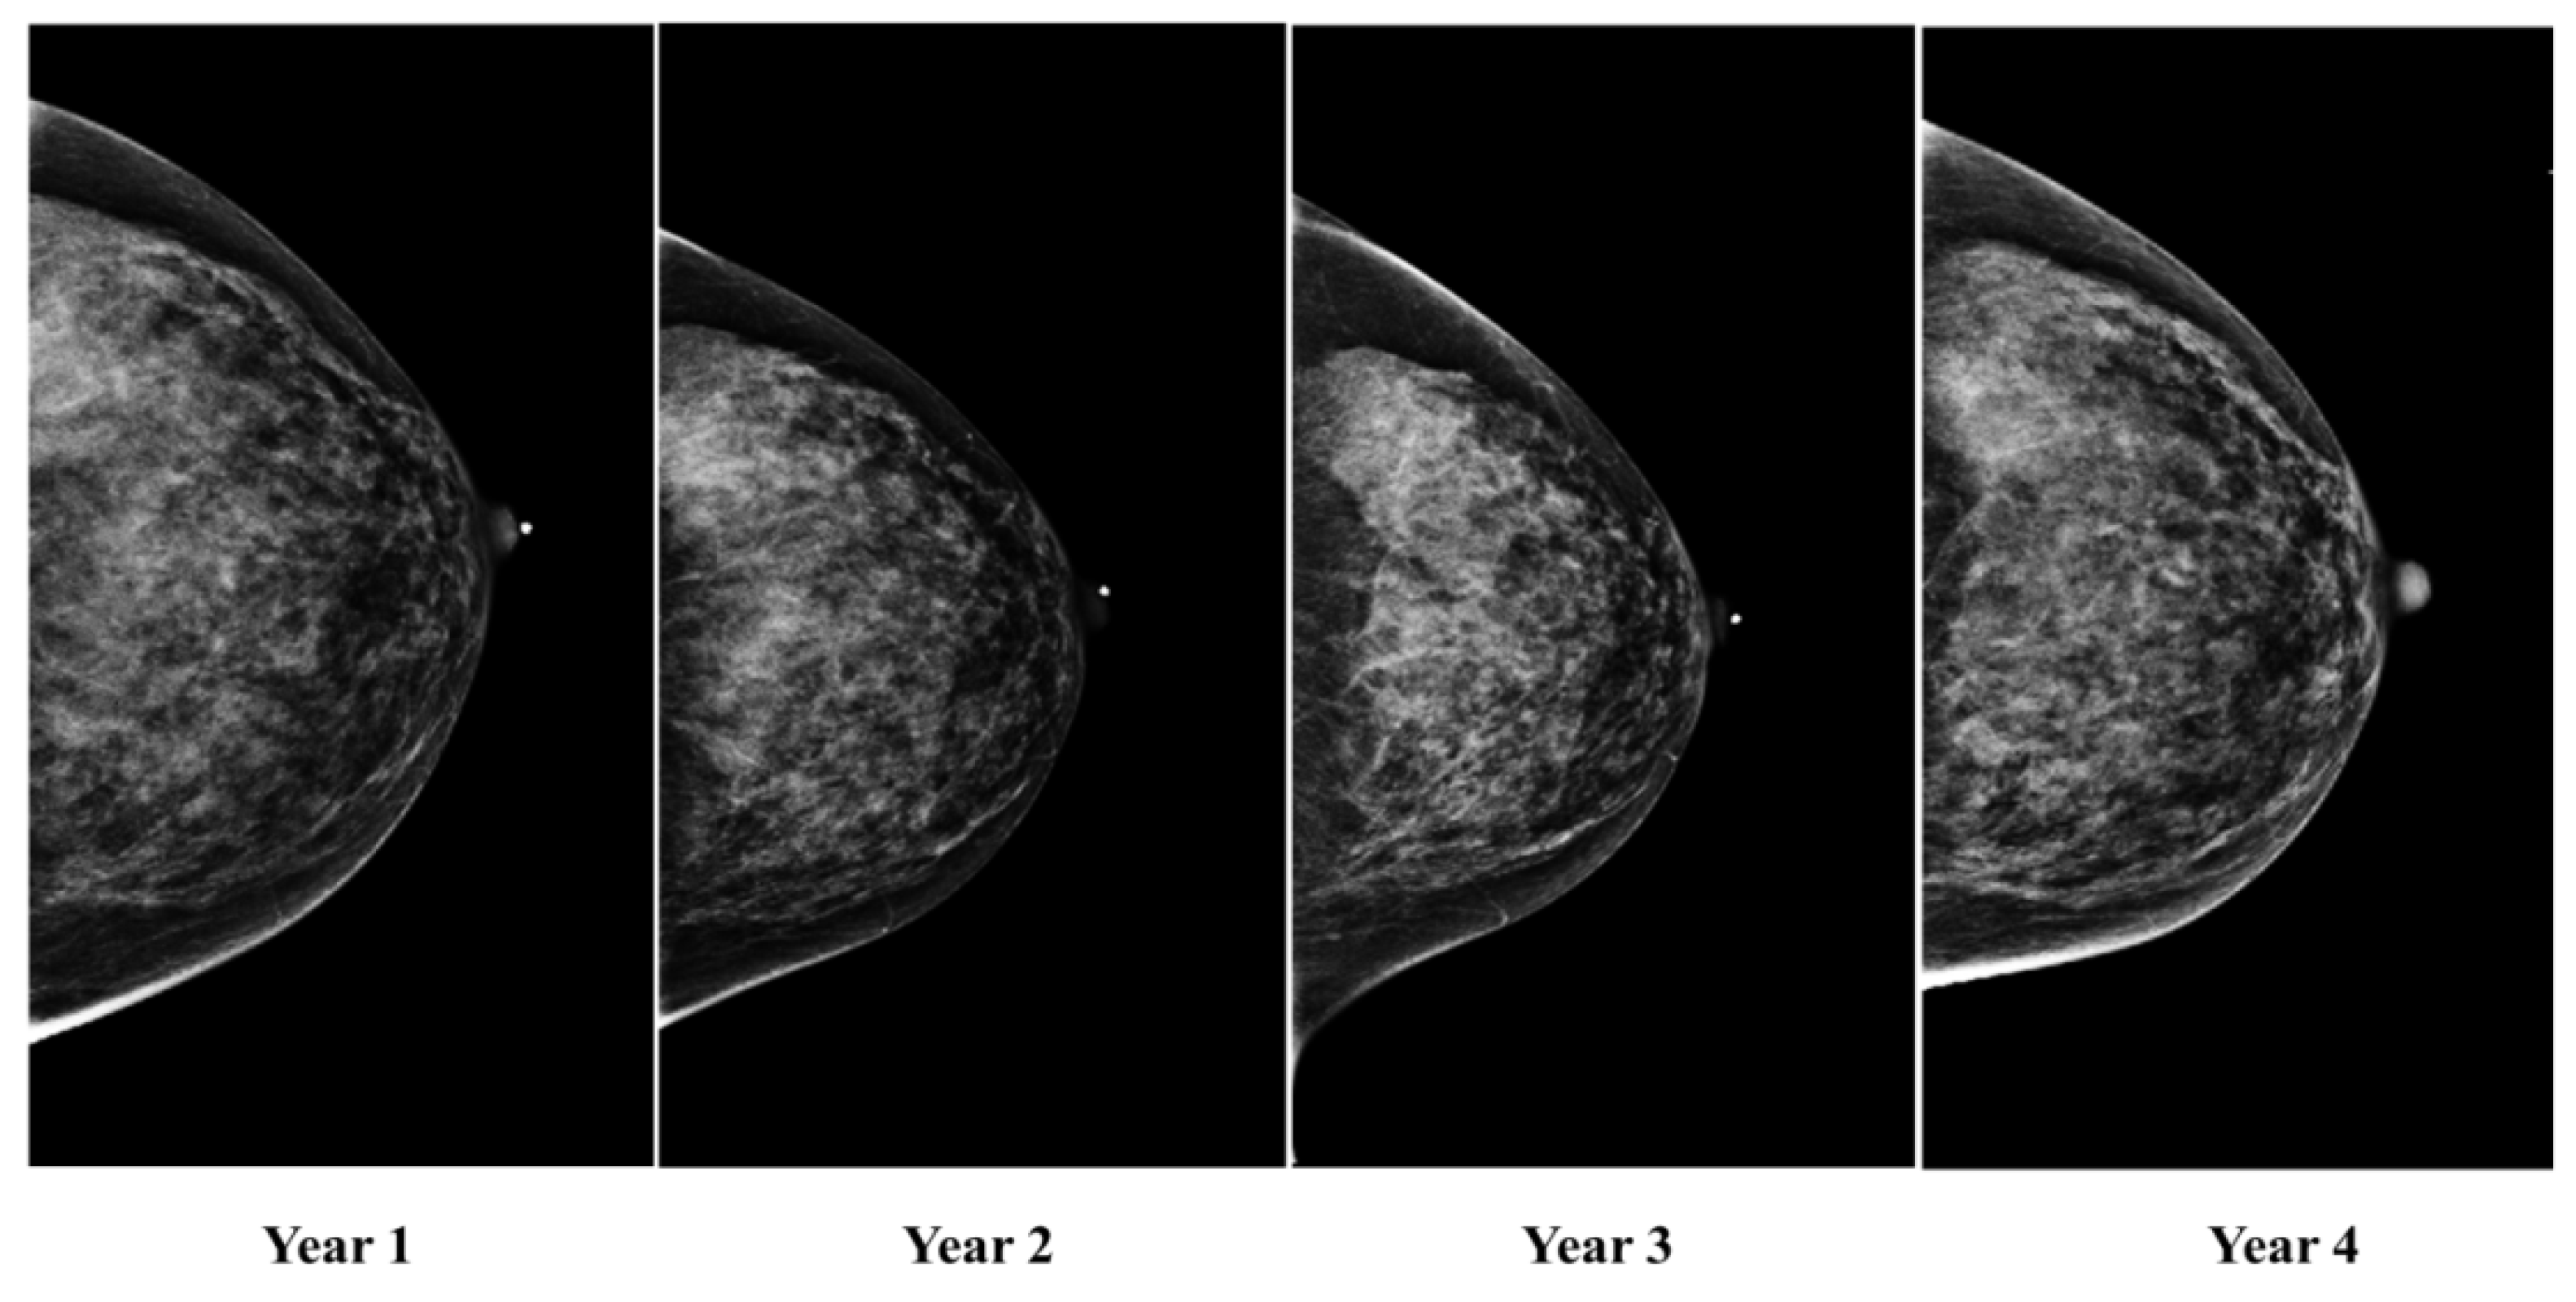

Temporal Machine Learning Analysis of Prior Mammograms for Breast Cancer Risk Prediction

2.1. Image Acquisition and Database Description